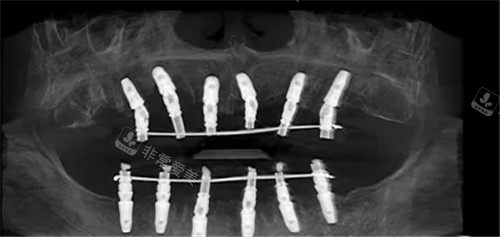

种植牙手术是一项精细且复杂的治疗过程,通常分为植体费、手术费、材料费等多个方面构成。在选择种植牙的过程中,除了价格因素外,还应考虑到医院的声誉、医生的资质和经验、手术设备的先进程度等因素。

一般来说,种植牙的费用主要包括:植体费用(植入牙根)、手术费用(手术过程中的医疗费用)、材料费用(包括种植体材料、义齿材料等)、术后恢复费用等。在选择种植牙的过程中,患者应该根据自身的实际情况和需求,多方面考虑这些费用因素。